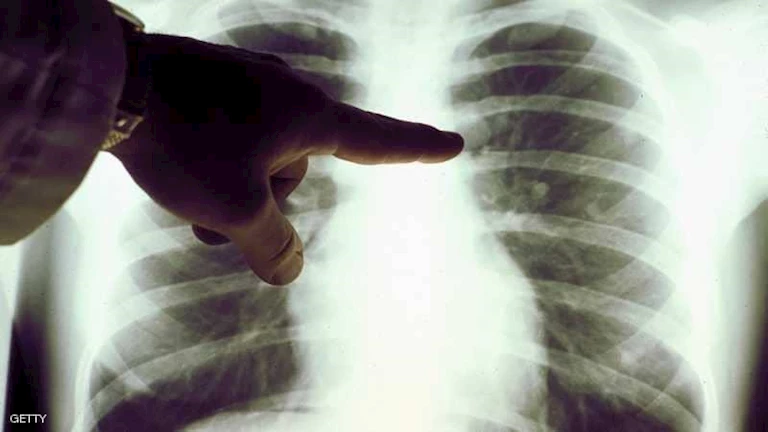

يُعد سرطان الرئة السرطان الأكثر انتشاراً عالمياً والسبب الرئيسي للوفيات المرتبطة بالسرطان. ويعقد الخبراء آمالهم الآن على أن يتمكنوا من منع ظهور أنواع معينة من السرطان بشكل أساسي.

سيصبح بإمكان المرضى الأكثر عرضة للإصابة بسرطان الرئة المميت الحصول على أول لقاح وقائي في العالم لهذا المرض. ومع ذلك، يظل الإقلاع عن التدخين هو التوصية الأفضل لتجنب الإصابة به.